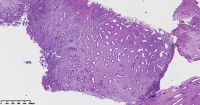

请老师们帮看看这些子宫内膜

性别

女

年龄

47岁

临床诊断

一般病史

子宫内膜息肉

标本名称

大体所见

图1

增殖性子宫内膜,子宫内膜息肉